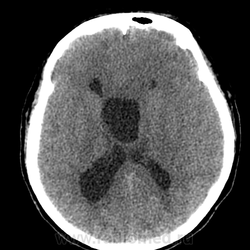

Эпидермоид может расти, при ТИА может быть случайной находкой. А тут ещё окклюзионная гидроцефалия.

Я бы может сказала что здесь агенезия мозолистого тела. Как мне не хватает МРТ данных (. Агенезия ? Перегородки. Сергей Николаевич подскажите возраст пожалуйста. Здесь должна быть выраженная неврологическая клиника. Расскажите побольше о пациенте.

Создается впечатление о нехватке/недостатке мозгового вещества.